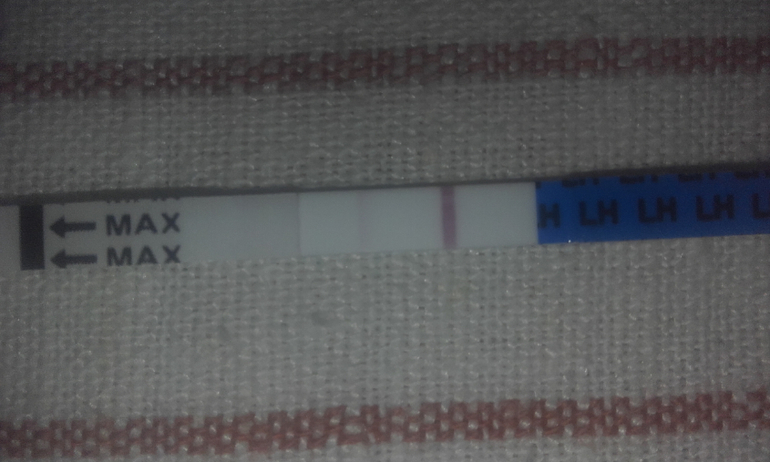

Девочки..я в шоке..вчеоа была на узи..ДФ 15 мм..Сегодня днем тест на О..Пока отрицательный..Но в предыдущие дни был вообще пустой..Сейчас пришла с приема от другог врача..Во первых даже не сделала осмотр..Во вторых даже толком снимки не смотрела и сказала что это все бред..ДФ нет и О не будет..Я расстроена это мягко сказать..Я в шоке...Прием длился 5 минут..

А чего расстроились то? Дф видно у вас на узи. 15 мм мало, для того чтоб тесты стали полосатится вовсю . Дня через 2 фоллик подрастет и Лг повысится,тогда и тесты станут положительными.

Сегодня 11